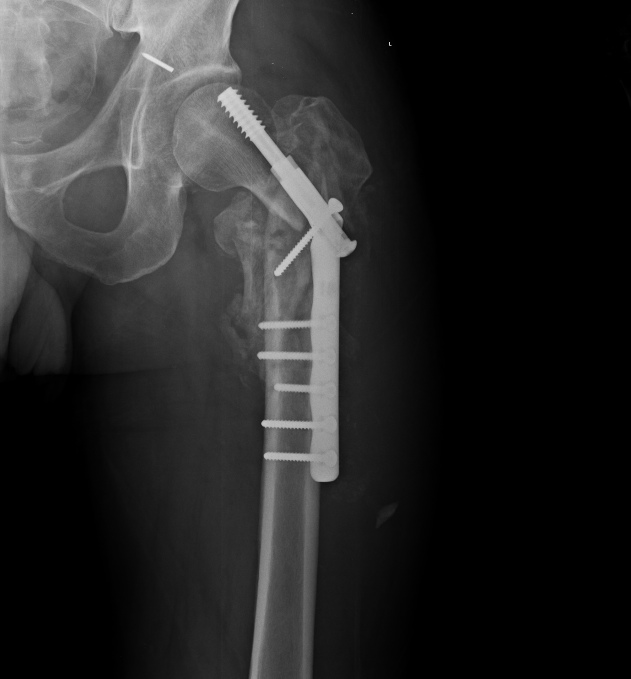

Мужчина 55 лет, оперирован полтора месяца назад в Прокопьевске.

Картина вот такая. Интересен еще и фрагмент спицы в вертлужной впадине. Ходит с костылями, не нагружая оперированную ногу.

Что будем делать? Оставить как есть и подождать? Клинковая пластина? Гвоздь? Сразу эндопротез? Что бы сделали?